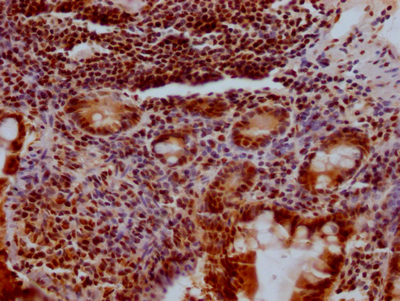

IHC image of CSB-RA194949A0HU diluted at 1:100 and staining in paraffin-embedded human colon cancer performed on a Leica BondTM system. After dewaxing and hydration, antigen retrieval was mediated by high pressure in a citrate buffer (pH 6.0). Section was blocked with 10% normal goat serum 30min at RT. Then primary antibody (1% BSA) was incubated at 4℃ overnight. The primary is detected by a Goat anti-rabbit IgG polymer labeled by HRP and visualized using 0.05% DAB.